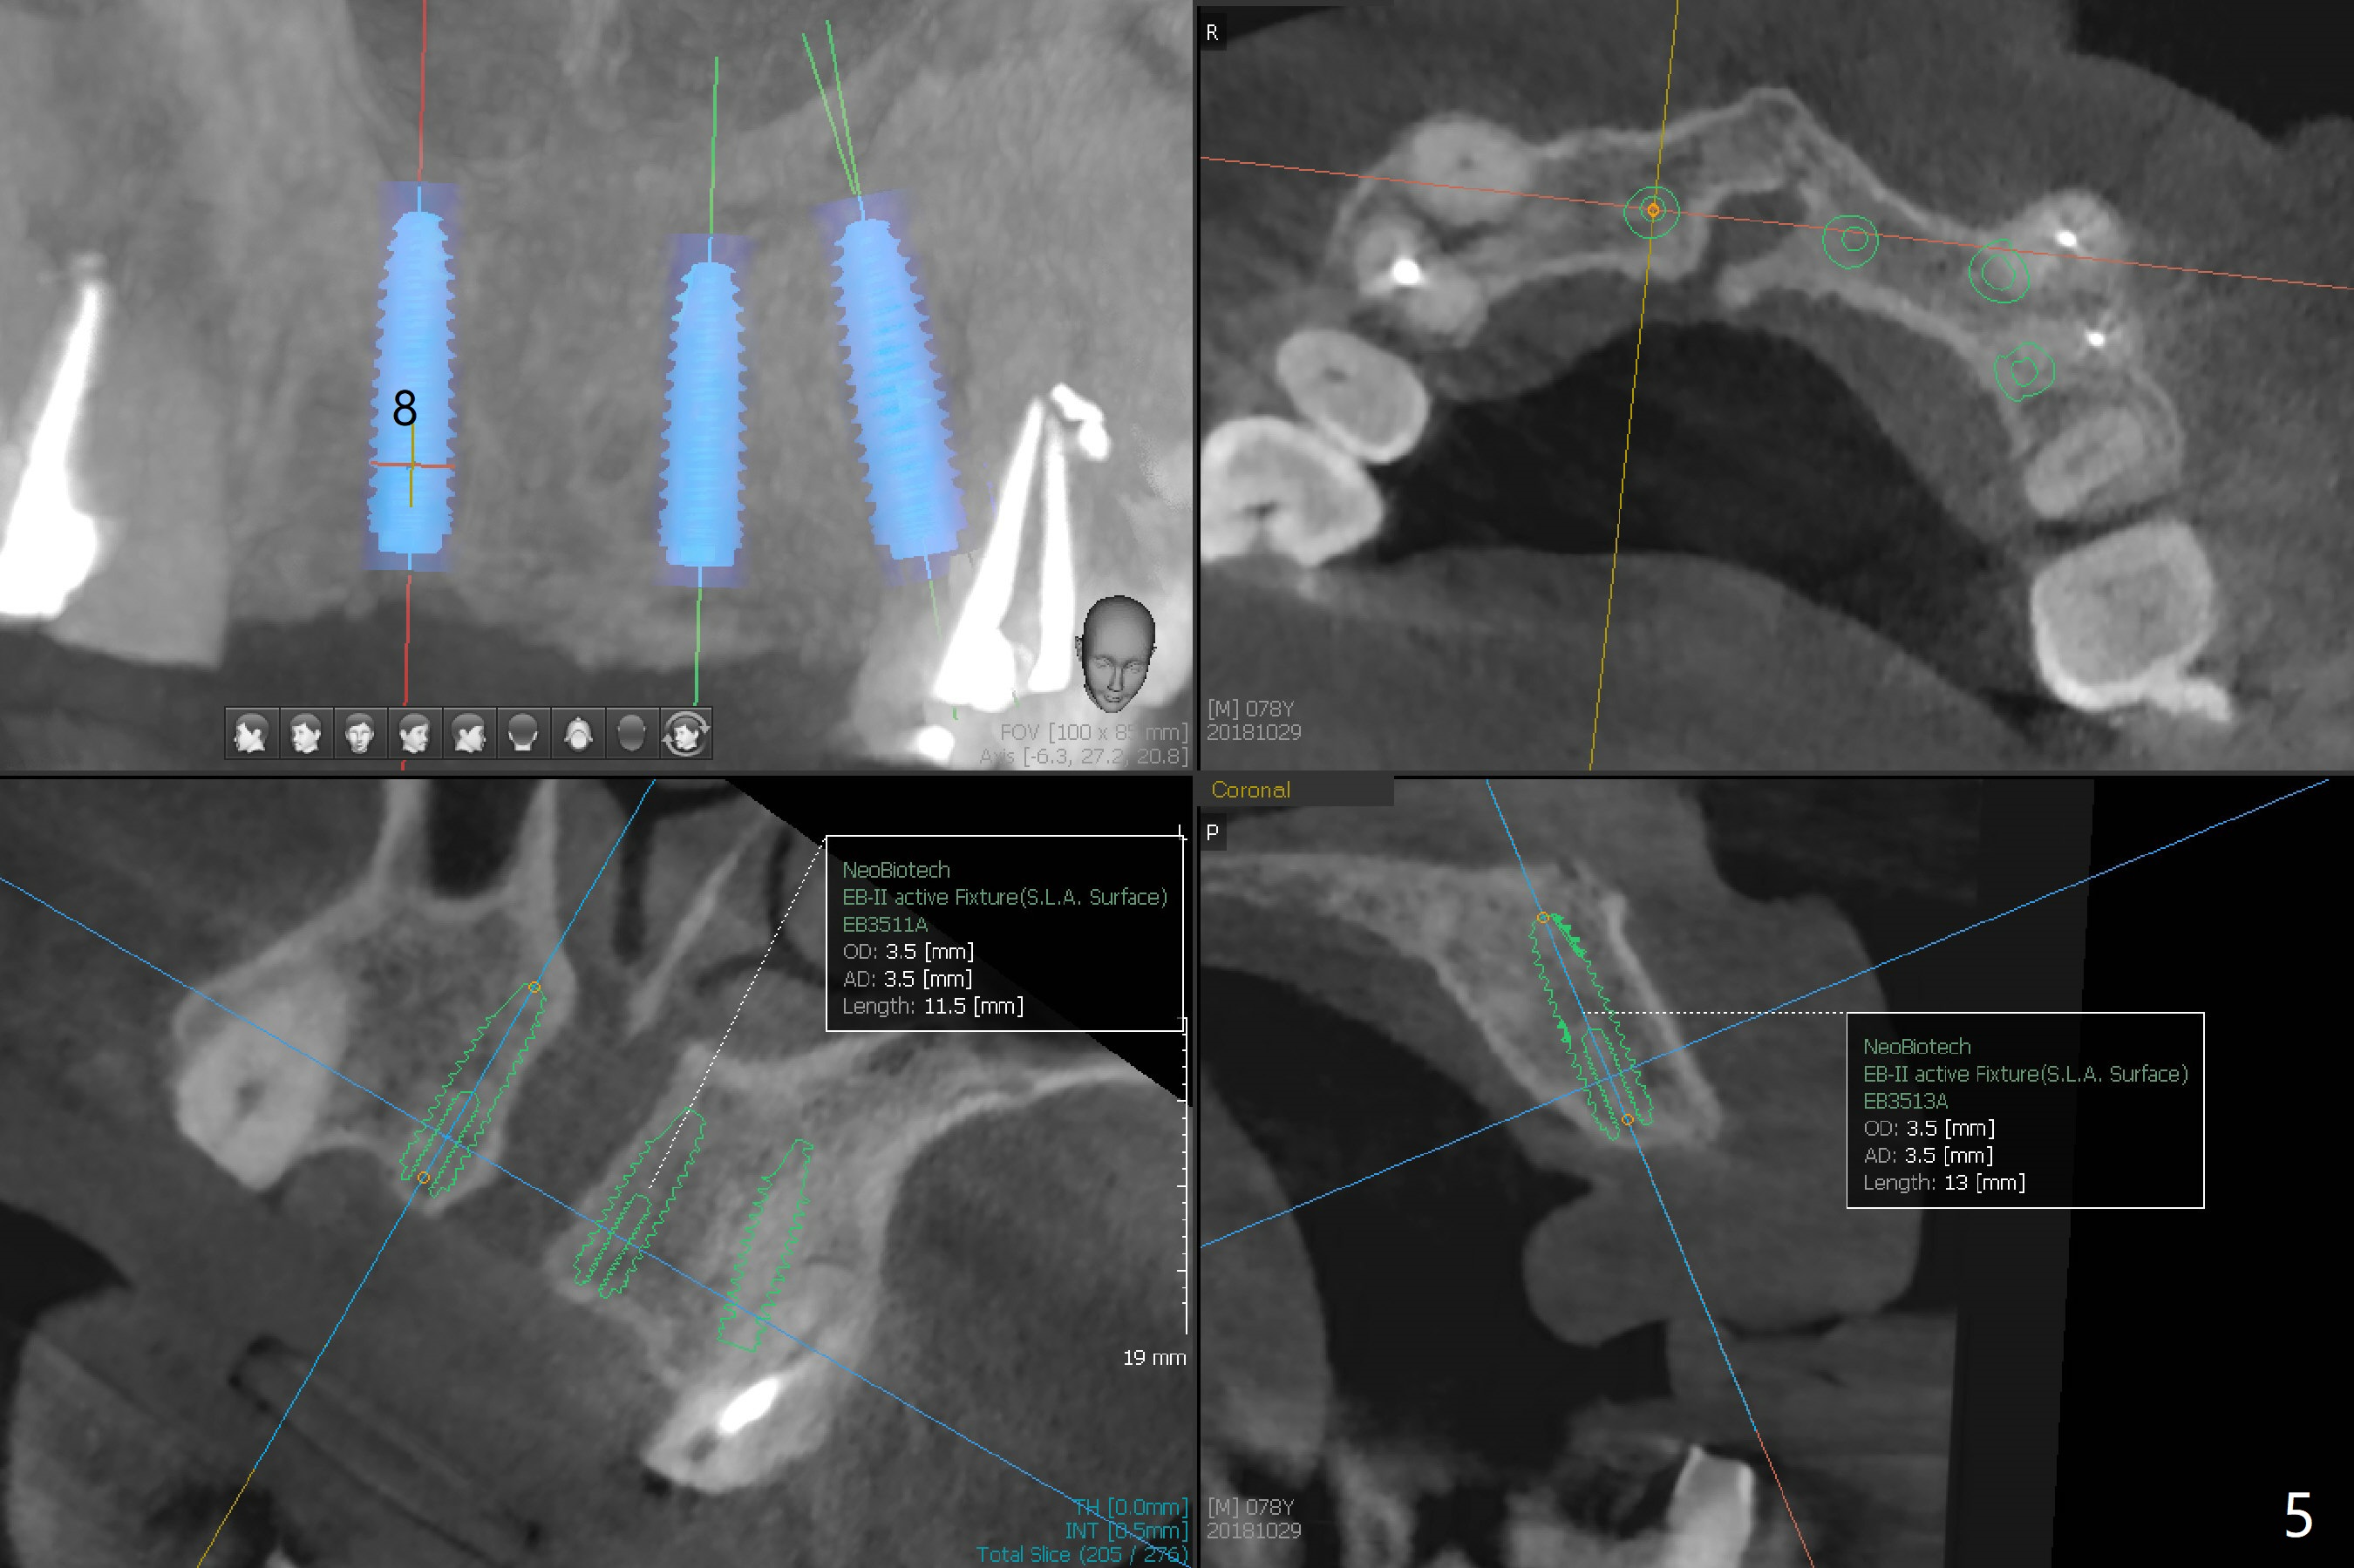

A 78-year-old man's 8 unit FPD dislodges (#5-12, Fig.1). Three of 4 abutments seem to be non-salvageable (#6,11,12 fractured equigingival, extraction, immediate implants). For restoration, implant will be placed at #8 and 9 as well. Implant FPDs will be fabricated at #6-8 and 9-11 (Fig.2) with #5 (with build up or prefabricated post) and 12 single unit crowns to better withstand deep overbite and overjet. After discussion with lab, a major change will be implants to be placed at #7 and 10 instead of #8 and 9 (narrow ridge). The implant at #7 will be a 1-piece (3 mm in diameter), whereas the rest 2-piece (3.5 mm). The abutment of IS 1-piece implant is 10 mm in length, while that of DIO's 5 mm. The former will be used if the vertical space is sufficient.